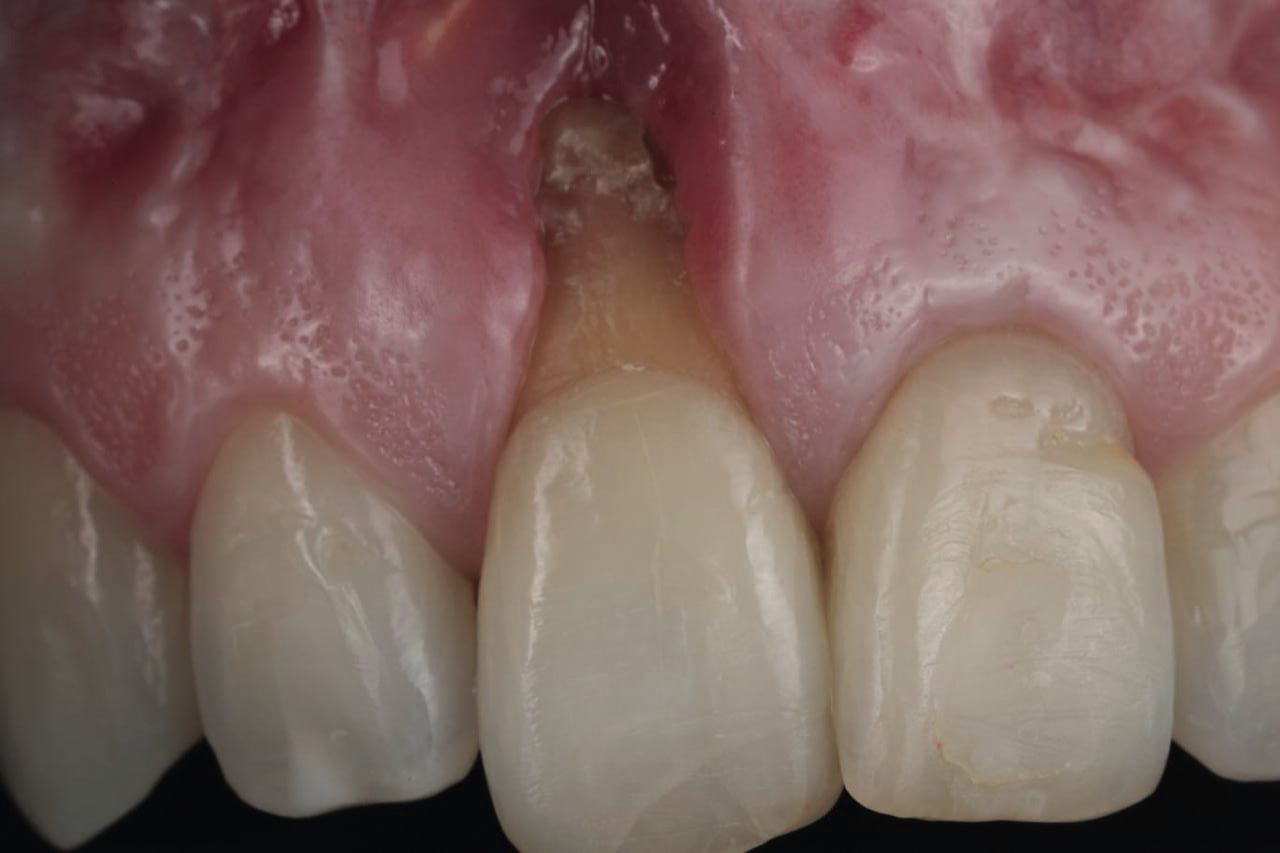

• Хирургические методы устранения рецессий

• Соединительнотканный трансплантат (СТТ)

• Пластика мягких тканей в области имплантатов